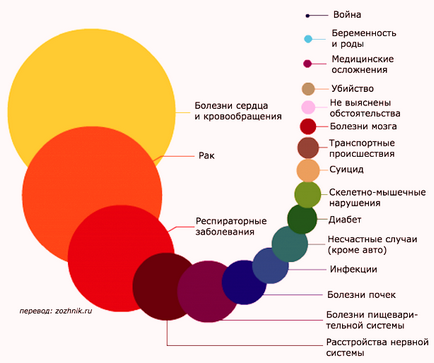

Явища, найчастіше викликають смерть, - це старіння. недоїдання. хвороби,

самогубство. вбивство і нещасні випадки

- Офіційна інформація про смертність.

Всесвітня організація охорони здоров'я (ВООЗ) (wiki) регулярно веде облік заблеваній, від яких люди вмирають у всьому світі. Особливо в країнах, що розвиваються, там зустрічаються такі захворювання, які в промислово розвинених країнах в даний час повністю зникли, або принаймні, їх можна вилікувати за допомогою сучасних ліків.

В багатших країнах, однак, люди, як правило, помирають від наслідків свого способу життя, таких захворювань, як подагра або діабет.

ОСНОВНІ ПРИЧИНИ СМЕРТНОСТІ В СВІТІ:

1. Ішемічна хвороба серця 13%

2. Інсульт. Цереброваскулярні захворювання 12%

3. ХОЗЛ - Хронічна обструктивна хвороба легень 6%

4. Респіраторні захворювання. Інфекції нижніх дихальних шляхів 5%

5. Кишкові інфекції 3,2%

6. СНІД та ВІЛ 3%

7. Рак легенів, рак трахеї 3%

8. Туберкульоз 2,7%

9. Діабет 2,7%

10. ДТП 2,1%